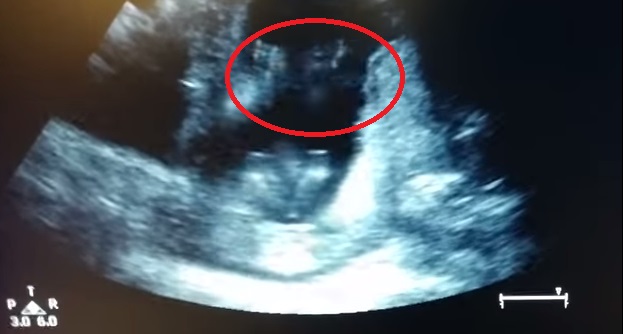

ROMA – Una donna incinta e suo marito vanno dal medico per effettuare un’ecografia alla 14esima settimana di gravidanza. Durante l’esame accade qualcosa di straordinario: il piccolo feto sembra battere le mani quando i genitori iniziano a cantare “Se sei felice e tu lo sai”.

Il video postato su YouTube dall’utente Jen Cardinal è stato probabilmente ritoccato, ma la reazione del bimbo è comunque adorabile. Secondo quanto spiegano i medici, alla 14esima settimana di gravidanza un bimbo riesce a muovere le labbra, inghiottire la saliva. Anche gli organi interni sono formati: diverse le opinioni dei medici sul fatto se sia in grado oppure no di reagire agli stimoli esterni. La teoria prevalente è quella che non sia ancora in grado di fare cose del genere, come muovere aqualche parte del corpo a ritmo di musica.